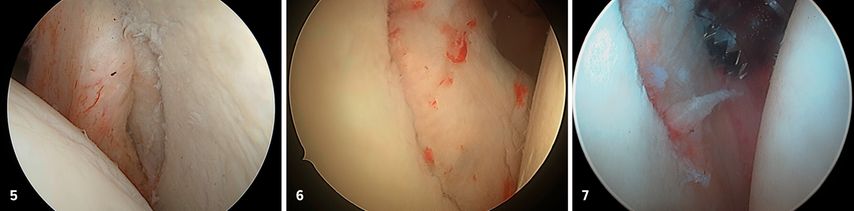

Zur definitiven Fixation stehen unterschiedliche Techniken zur Verfügung. Die arthroskopisch assistierte Schraubenosteosynthese wird meistens durch das 5-Uhr-Portal durchgeführt. Kanülierte Schrauben (2,7–3,5mm) bieten, insbesondere bei größeren, kompakten Fragmenten, eine hohe Primärstabilität, ihr Einsatz ist jedoch technisch anspruchsvoll und mit dem Risiko einer intraartikulären Implantatprominenz verbunden. In den letzten Jahren sind aber Systeme mit bioresorbierbaren Implantaten hinzugekommen, die für die vordere Glenoidaugmentation entwickelt wurden (Abb. 5). Dieses System eignet sich auch perfekt für die Fixation des Glenoidfragments.